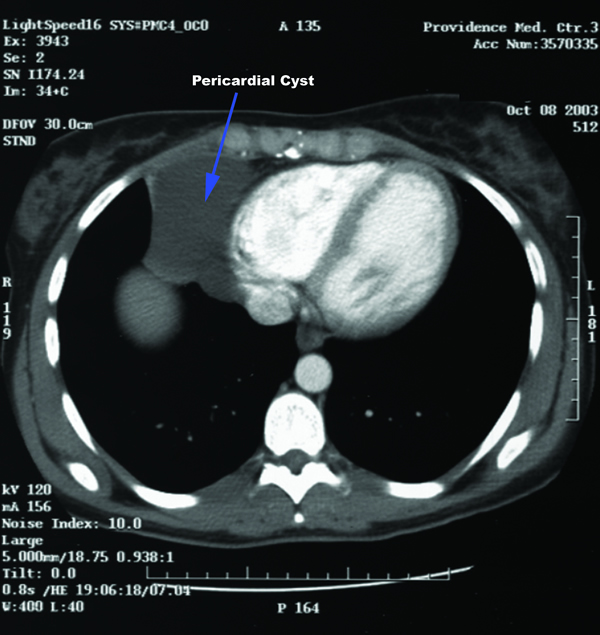

Patient is a 29 year old female, who was diagnosed with a pericardial cyst when she was 17 years old during a work-up of asthma. Recently, the patient presented with a persistent cough, and a repeat CT scan revealed increase in size of the cyst to approximately 6x6cm (Figures 1 and 2). Her past medical history was significant for Wolff-Parkinson-White syndrome. On examination no abnormalities were found. Since the cyst was enlarging, causing significant anxiety, and possibly contributing to her persistent cough, resection was recommended. Her cardiologists felt that her WPW Syndrome was not a contraindication to surgery.

| Figure 1. Preoperative Chest x-ray. | Figure 2. Chest CT scan showing right cardiophrenic pericardial cyst. |

Contrast CT scan has been the modality of choice to diagnose and to follow pericardial cysts[1,2]. However, no studies have been done to ascertain the superiority of contrast CT over MRI and echocardiography for diagnosis or for follow-up. On CT scan pericardial cysts are thin-walled, sharply defined, oval homogeneous masses . Their attenuation is slightly higher than water density – 30 to 40 HU[8]. They fail to enhance with intravenous contrast[8]. The frequency of follow-up imaging has not been established.